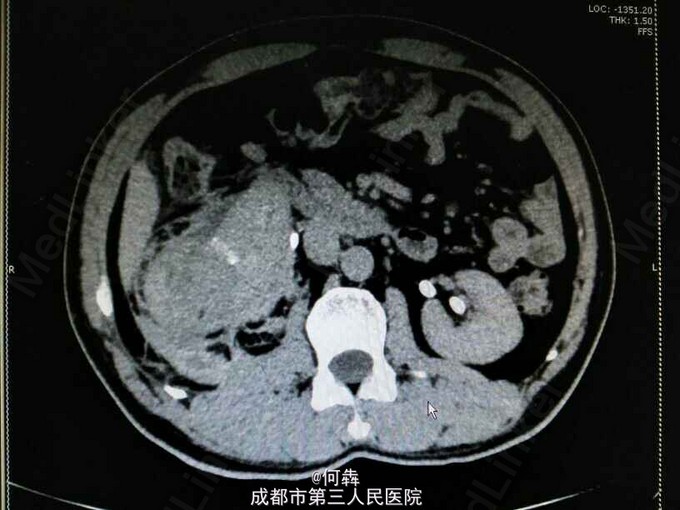

48岁男性,因“突发右腰痛1小时”入院,无血尿、外伤。既往无高血压、糖尿病。

右肾区扣痛阳性,余阴性。

右肾占位伴出血。入院后6天在全麻下行右肾部分切除术。术中冰冻及术后病检见图片